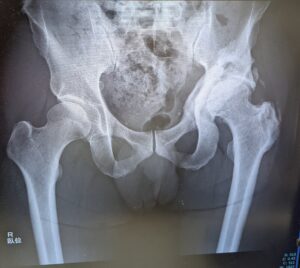

レントゲンは直ぐに呼ばれて、臥位と立位で合計3枚撮影。

- 異所性骨化巣の再発はなし